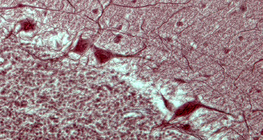

zumiranje: 100x